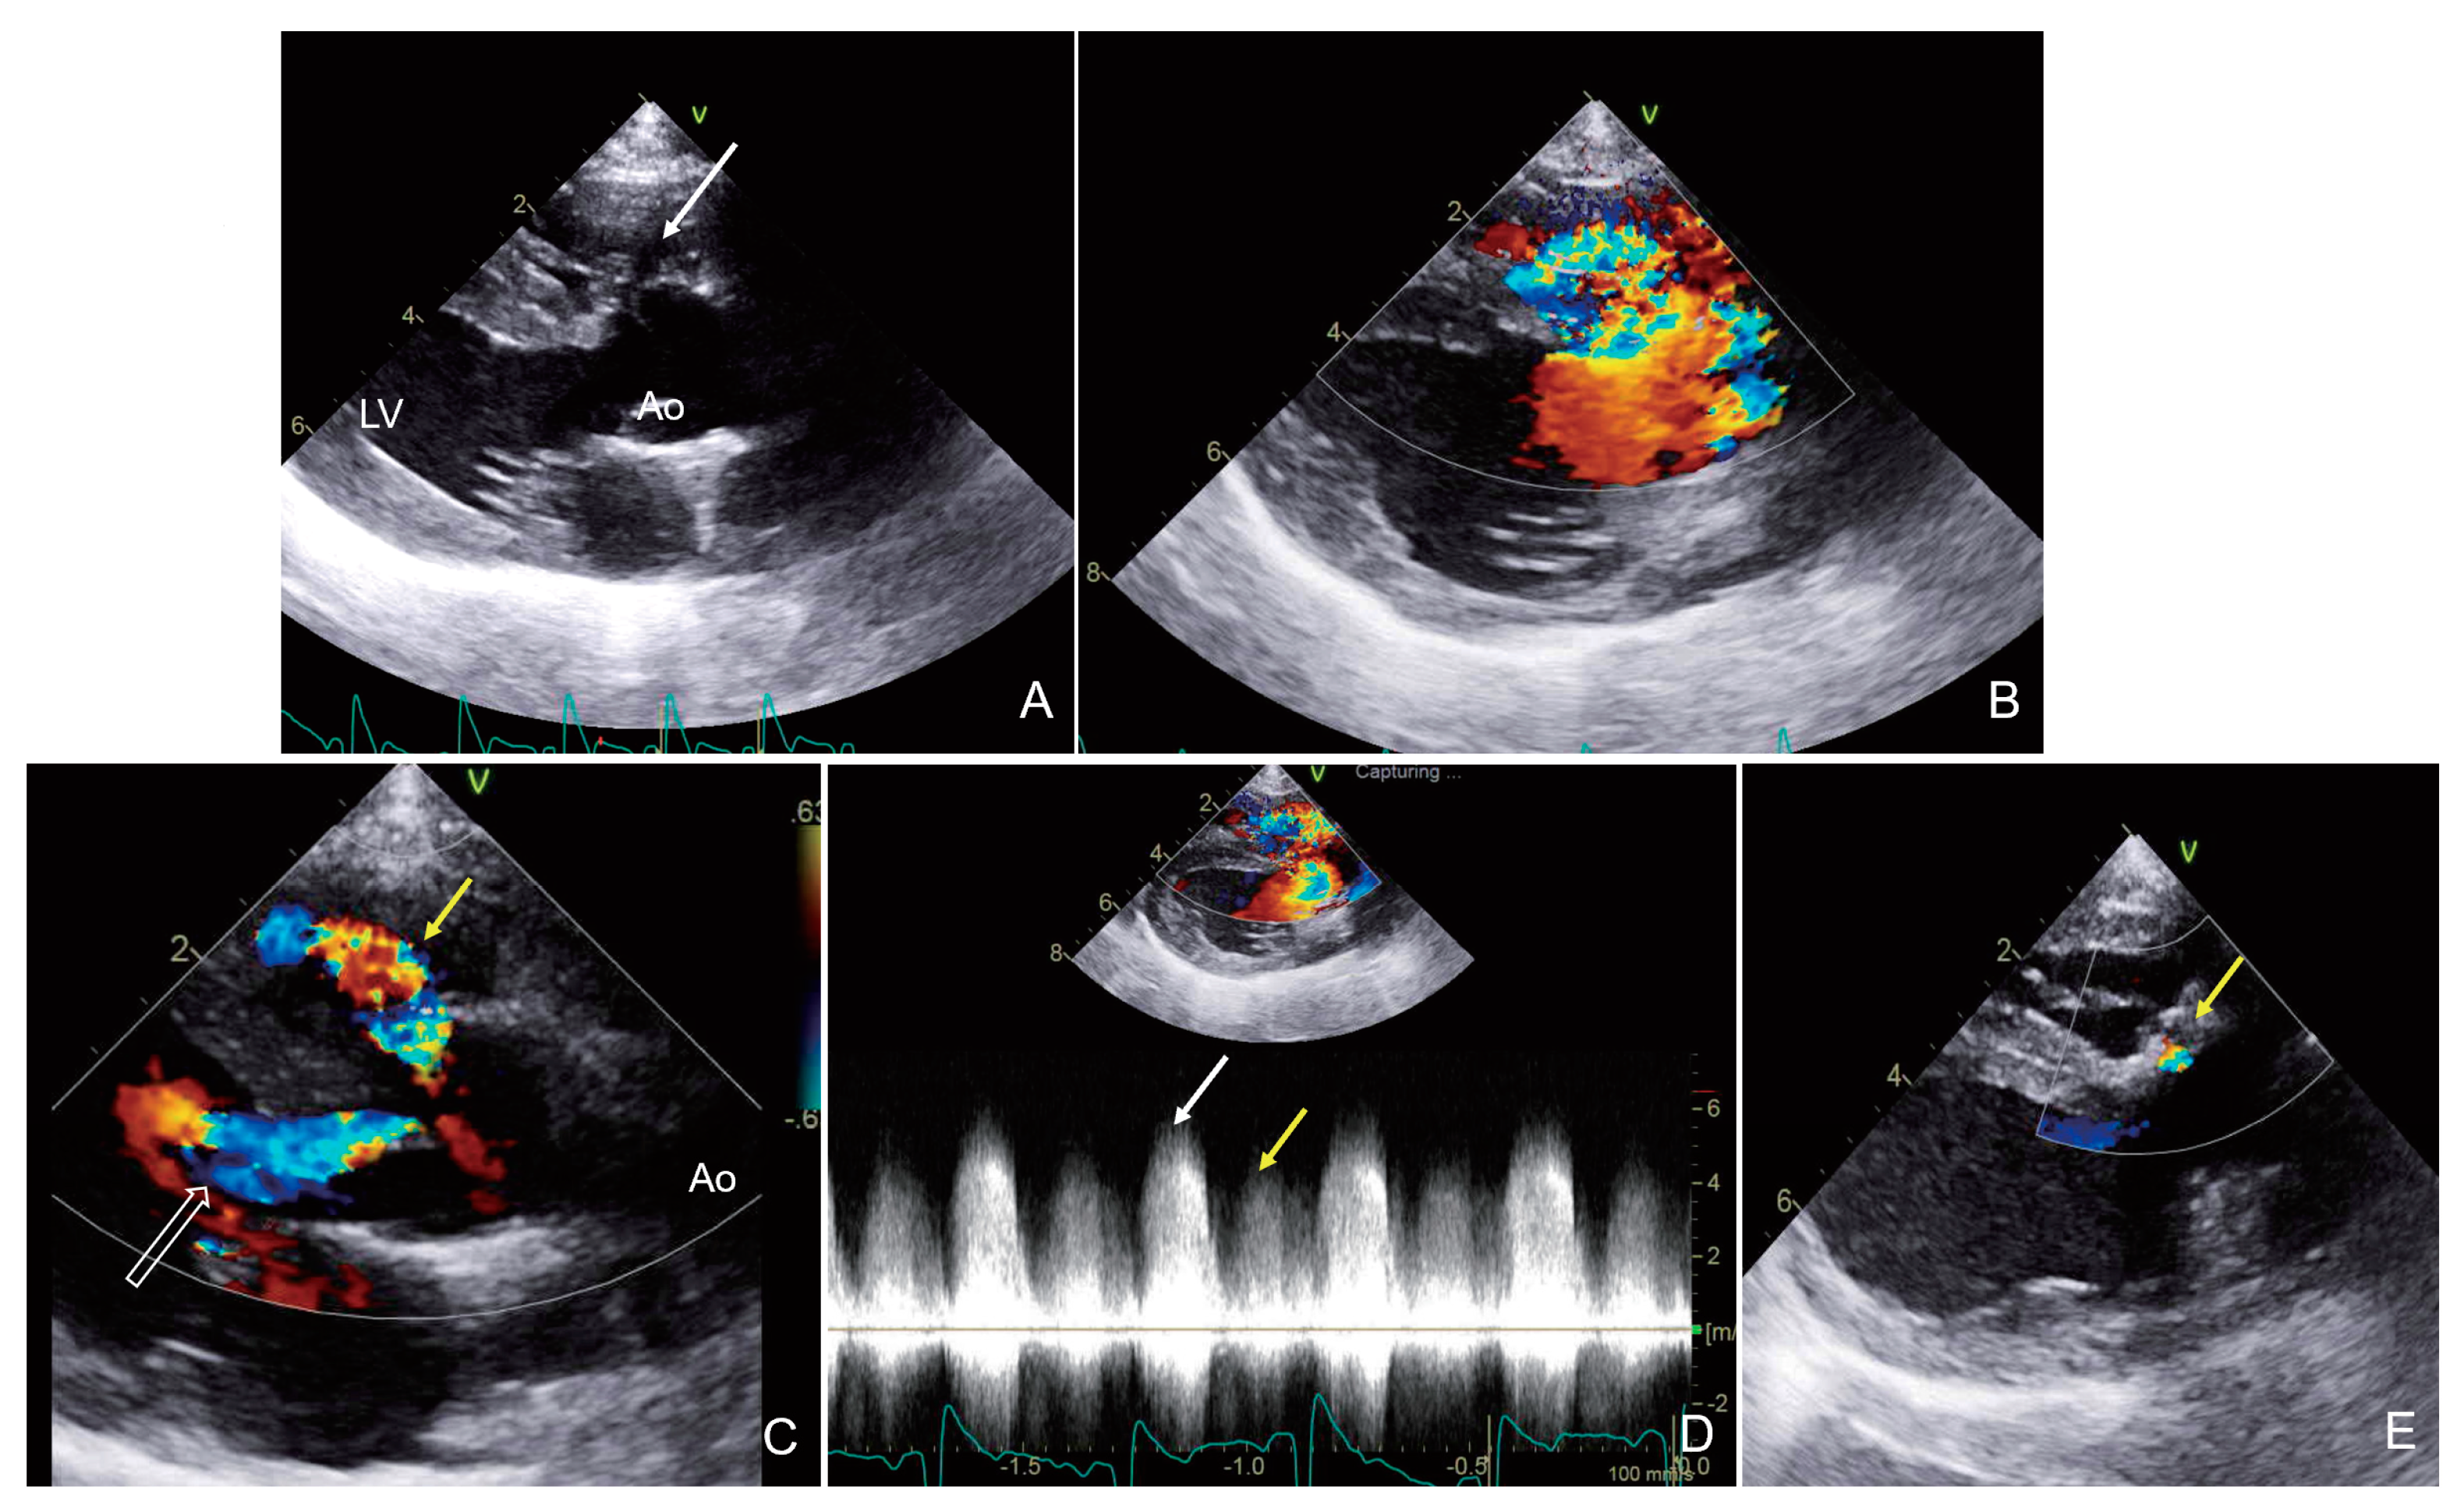

2.1. Case 1